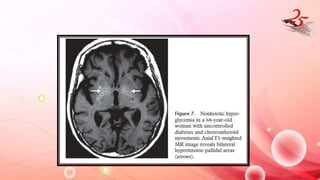

NON KETOTIC HYPERGLYCEMIA

• CLINICAL FEATURES : poorly controlled diabetes with chorea ,

hemiballismus +/- altered mental status.

• Treatable condition which shows resolution of findings when

performed 2-12 months later

IMAGING FINDINGS

⁻ CT: B/L or rarely U/L hyperattenuation of GP or CN

⁻ MR : hyperintensity on T1 and variable intensity in T2